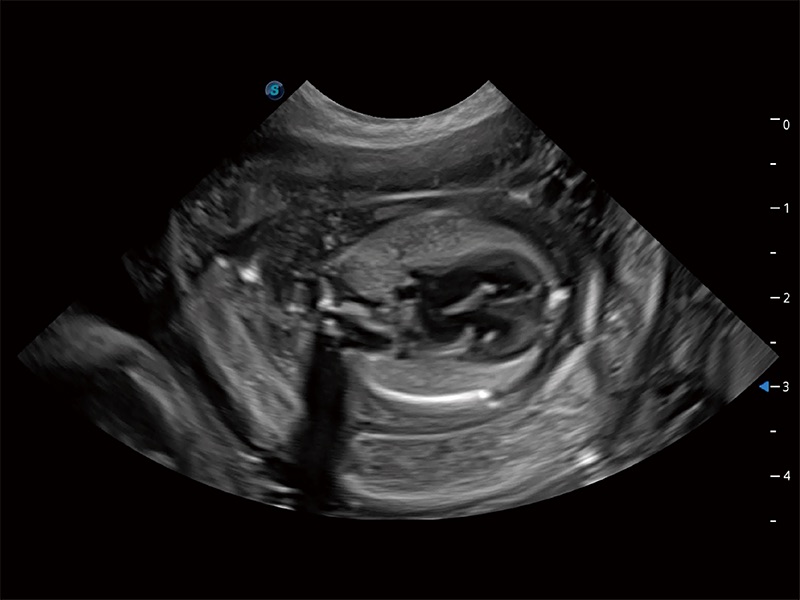

动物是人类最亲密的朋友和最值得信赖的伙伴。16877太阳集团也一直致力于探索动物专用的超声影像解决方案。全新推出的ProPet系列,是16877太阳集团在动物超声影像智能化、专业化、精准化的一次跨越式革新。动物不能用言语来表述自己的不适,通过超声影像,ProPet系列搭建了动物医生与不同物种沟通的“桥梁”,为动物医生注入了“治愈之力”。 ProPet 80 是16877太阳集团匠心打造的一款高端动物专用彩超,采用性能卓越的全新硬件架构,极大提升超声系统的运行效率和数据处理能力,帮助动物医生从容应对日益增多的挑战性病例和日益多样化的临床需求。

高性能和先进的临床应用工具可以为动物医生提供临床信心。ProPet 80 搭载了先进的腹部和浅表应用工具,帮助医生在日常临床实践中发挥前所未有的作用。

ProPet 80 专为动物医生设计,对不同的动物体型和生理结构作出了针对性的优化。通过动物影像专用软件,可满足个性化的应用需求,帮助动物医生获得更精确的诊断数据。